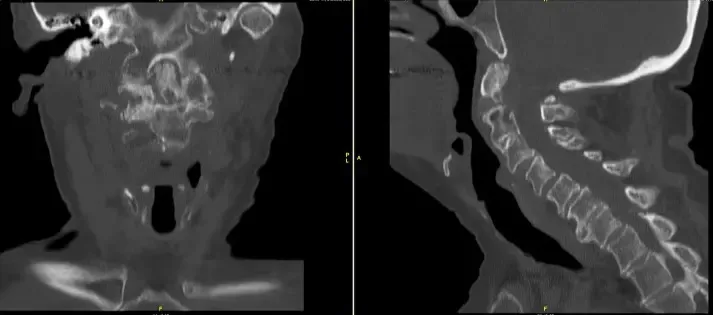

He was having balance issues along with weakness in all 4 extremities. X rays, CT scan and MRI showed a non-union of odontoid fracture with pannus formation and fibrous union, instability with compression of spinal cord at C1-2 level.